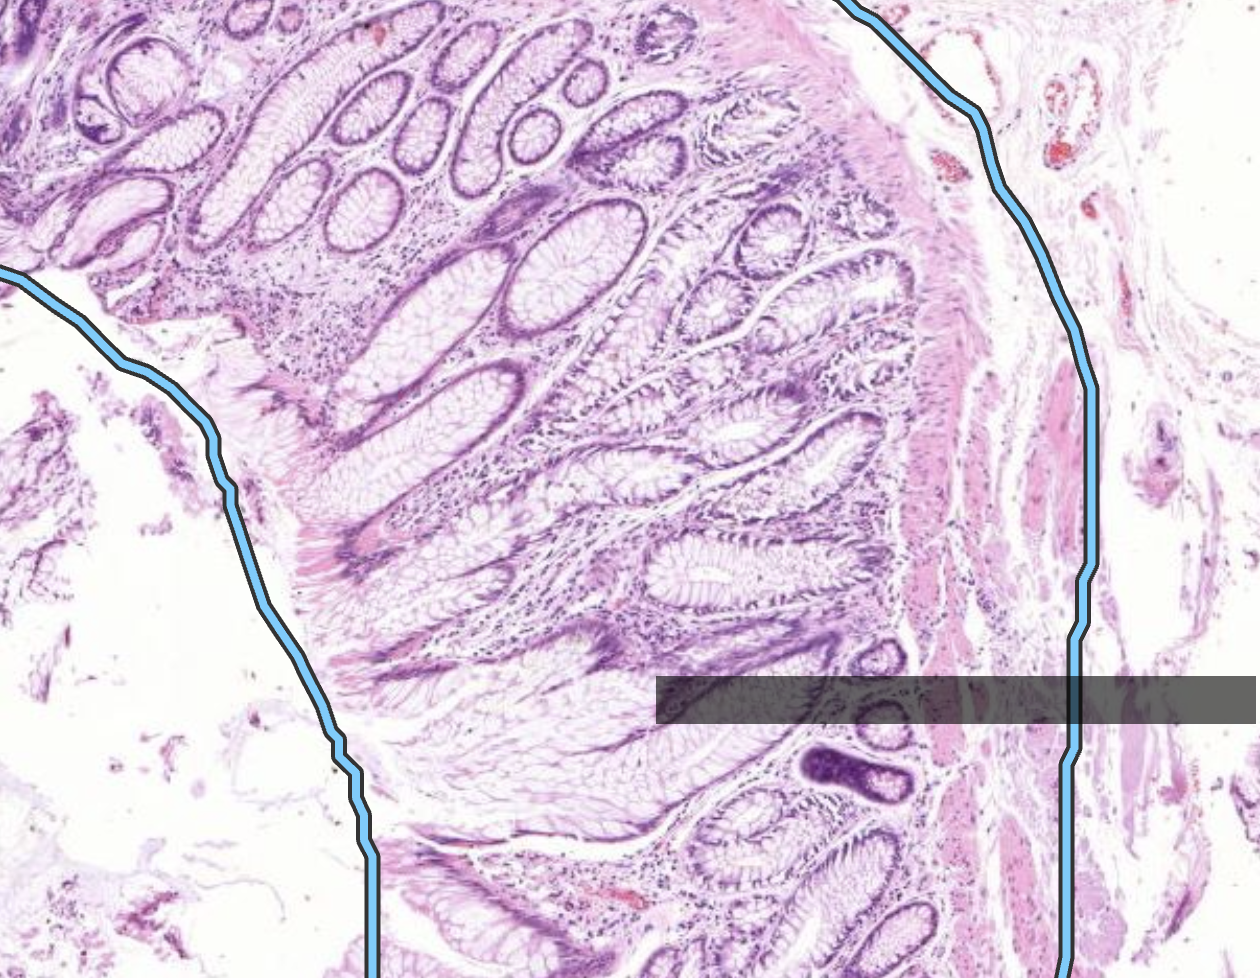

40) Welches Präperat ist hier zu sehen?

Histopathologisches Bild: Kolonschleimhaut

Hier zu sehen ist eine Lipom im Kolon.

Es ist als gutartig anzusehen, weil die Fettzellen stark differenziert sind und keine Zellveränderungen zu sehen sind.

Man erkennt erst das es ein Tumor ist, weil es sich Gewebsdrägend verhält, die darüberliegende Colonschleimhaut wird schmal erdrückt.